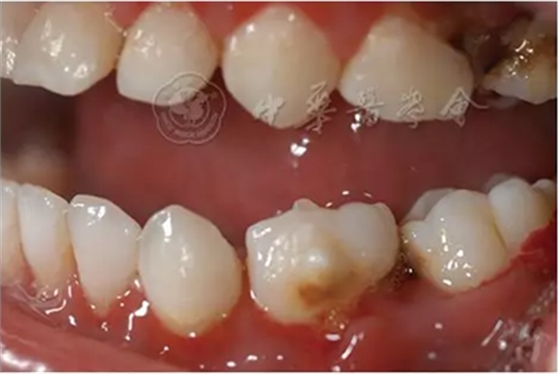

(1)疾病定義及口腔表現(xiàn):中性粒細(xì)胞減少是由于外周血中粒細(xì)胞的絕對(duì)值減少而出現(xiàn)的一組綜合征。出生后2周至1歲的嬰幼兒中性粒細(xì)胞低于1×109/L、1歲以上兒童中性粒細(xì)胞低于1.5×109/L時(shí),即可診斷為中性粒細(xì)胞減少癥。當(dāng)中性粒細(xì)胞低于0.5×109/L時(shí)則可診斷為粒細(xì)胞缺乏(agranulocytosis)。根據(jù)中性粒細(xì)胞減少的程度和持續(xù)時(shí)間,病情的輕重不同。病程初期為發(fā)熱,之后表現(xiàn)為反復(fù)感染且難以控制,好發(fā)于呼吸道、泌尿系、皮膚和黏膜等。在口腔主要表現(xiàn)為反復(fù)發(fā)作的口腔炎、口腔潰瘍,牙齒松動(dòng)、乳牙早失,牙齦紅腫、糜爛、齦袋溢膿及牙槽骨喪失等(圖1)。

圖1 4歲中性粒細(xì)胞減少患兒乳牙牙齦明顯紅腫、糜爛